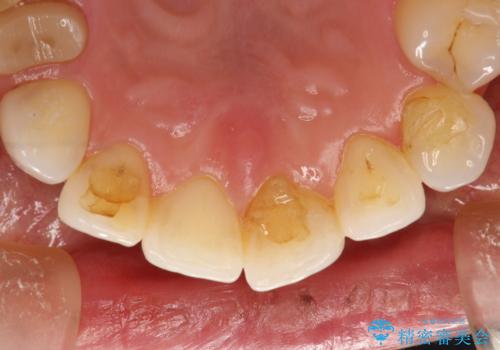

PMTC30分コース(保険外治療)を行いました。かなり久しぶりの歯科医院へ来院とのことで、プラーク(歯垢)・歯石・ステイン(着色)が付着していました。汚れを除去し、本来のご自身の歯質にすることでなにか異常があった際に発見しやすくなります。

また、今回はクリーニング後に、何か所か虫歯や治療途中のままの部分が発見されました。今後は定期的なメンテナンス・クリーニングと併用しながら虫歯の治療を行っていく予定です。